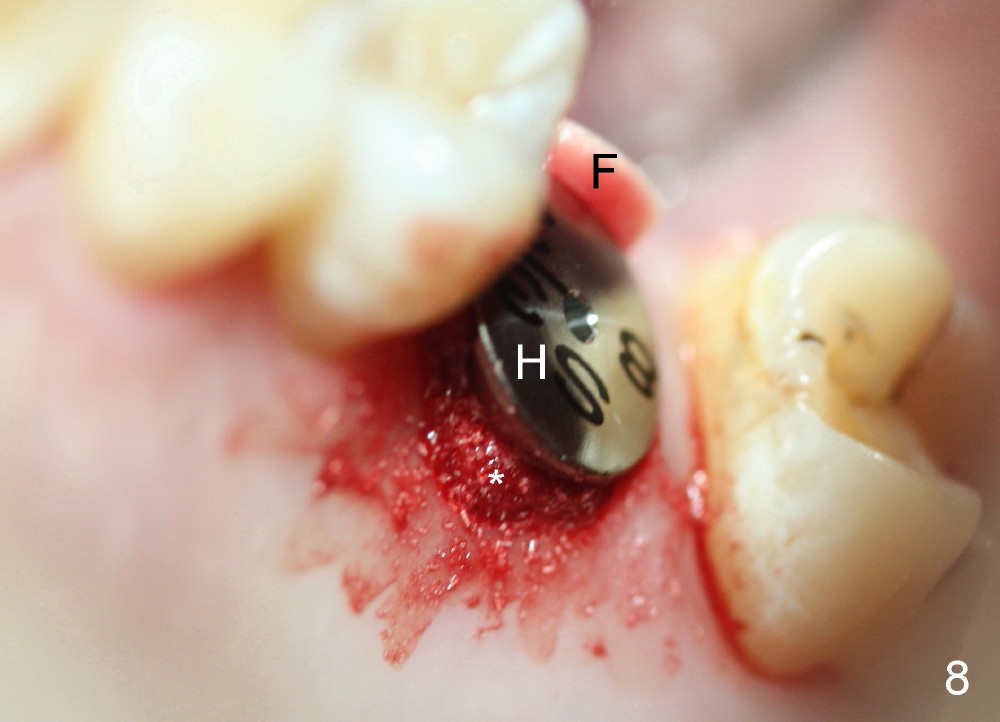

A 45-year-old man has lost the tooth #14 for a while (Fig.1); bone height is 5.4 mm. An extra wide and short implant is planned. Torus palatinus is large, suggesting that bone density should be high. A 6 mm tissue punch is chosen, but it is placed more palatal. If it were placed in the middle of the ridge, there would be no buccal keratinized gingiva (incision may avoid this issue). Additionally, the buccal portion of punch is made incomplete so that there is pedicle on the buccal side when the flap is raised (Fig.4,8: F). It is expected that the excess portion of keratinized tissue will form thick gingiva buccally. Osteotomy proves that bone is dense (Fig.2 (4.5x11 mm tap). Typical sinus lift is finished with placement of 6.4x6 mm (extra wide) bone-level implant (Fig.3, >55 Ncm). Following further torque, Fig.4 shows that the implant (I) is sub-gingival (<). Bitewings are taken to confirm that the implant plateau is at the crestal level (Fig.5,6 ^). PA shows sinus lift (Fig.7 *). The lingual aspect of the implant and healing abutment (H) is further bone grafted and covered by collagen dressing (Fig.8 *). The wound is protected with perio dressing. When the latter dislodges 7 days postop, the collagen dressing and bone graft are lost as well (Fig.10), while the buccal flap remains vital (Fig.9). The lingual exposed plateau should be able to heal normal. The collagen dressing should have been fixed in place by suture or as simple as a dental floss. There is mild nasal hemorrhage 1-2 days postop, possibly related to sinus membrane perforation and inability of Collagen Dressing to cover the perforation and contain the bone graft. When the patient returns for #9 implant placement in 3 weeks postop, the buccal flap reduces in size (Fig.11 *), while the palatal wound has healed with minimal exposure of the implant (Fig.12). Sinus graft remains in place 3 months postop (Fig.13); the buccal flap appears to have incorporated into a part of the gingiva (Fig.14). The bone density of the sinus lift appears to increase 10 days later when an abutment is placed (Fig.15 *). Although oral hygiene is pristine, there is apparent crestal bone resorption 12 months (Fig.16) and 20 months (Fig.17) post cementation, probably due to unfavorable crown/implant ratio and bruxism as well as pre-implantation bone loss (Fig.18,19). In contrast, an immediate implant in the same patient avoids pre- or post-implantation bone loss. In fact both the soft (Fig.20) and hard (Fig.21) tissues remain healthy 2 years 8 months post cementation. The sinus lift remains 3 years 8 months post cementation (Fig.22), while the crestal bone loss persists. The patients keeps complains of food impaction distal associated with bad smell 4 years 1 month post cementation. In fact the distal proximal contact is within normal limit. The bad smell is probably due to crestal bone loss (Fig.23 (pan), 24 (CT) *) and periimplantitis. Bone graft, PRF and Cytoplast membrane will be needed and fixed in place with long healing screw. When the patient returns for crown redo, he also reveals floss related gingival hemorrhage. There is pain associated with palatal sulcus probing with light gingiva erythema. Review of CT coronal section shows possible palatal (Fig.25 P) bone loss (*).